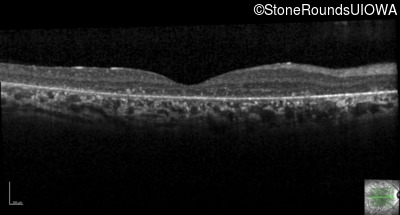

Optical Coherence Tomography - Right - 20/40 -1

Exemplar / OCT Stack

OCT Stack